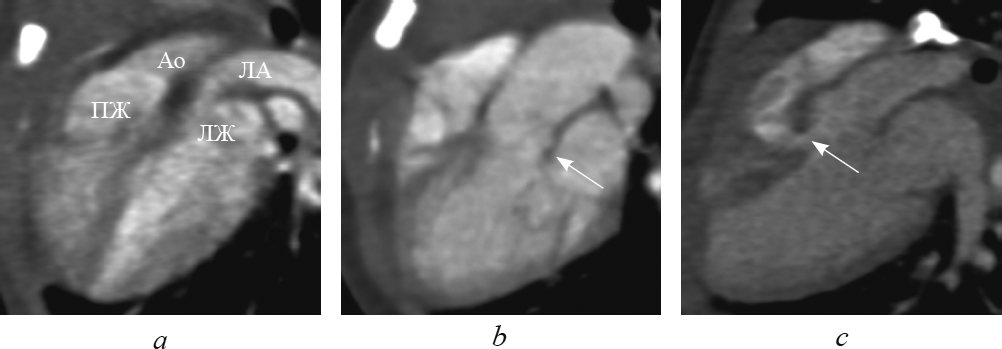

При транспозиции в этой реформации, в отличие от нормы, выходные тракты и магистральные артерии расположены параллельно. При этом визуализируются два параллельно расположенных сосуда: аорта — спереди от легочной артерии, которая является продолжением правого желудочка; легочная артерия — кзади от аорты, которая является продолжением левого желудочка (рис. 7, а). Параллельный ход магистральных артерий четко визуализируется и в реформации приточных отделов желудочков.

Рис. 7. В реформации по длинной оси левого желудочка при транспозиции магистральных сосудов: выходные тракты и магистральные артерии расположены параллельно (а); определяются митральное полулунное фиброзное продолжение (b, стрелка) и дефект межжелудочковой перегородки (c, стрелка). Ао — аорта; ЛА — легочная артерия; ЛЖ — левый желудочек; ПЖ — правый желудочек

Fig. 7. Long-axis of left ventricle reformation in great arteries transposition: outflow tracts and great arteries are parallel (а); semi-lunar fibrous prolongation (b, arrow) and interventricular sept defect (c, arrow) are determined. Ао – aorta; ЛА – pulmonary artery; ЛЖ – left ventricle; ПЖ – right ventricle

Достоверно визуализировать митрально-полулунное фиброзное продолжение, представляющее собой фиброзный контакт легочного клапана с митральным клапаном, при транспозиции удалось в 10 случаях (рис. 7, b). Дефект межжелудочковой перегородки визуализировался во всех случаях (рис. 7, c). В реформации по длинной оси левого желудочка удалось определить стеноз выходного тракта левого желудочка (рис. 8).

Рис. 8. В реформации по длинной оси левого желудочка при транспозиции магистральных сосудов определяется сужение выходного отдела левого желудочка. Ао — аорта; ЛА — легочная артерия; ВО — выходной отдел; ДМЖП — дефект межжелудочковой перегородки; ЛЖ — левый желудочек; ЛП — левое предсердие; ПЖ — правый желудочек

Fig. 8. Long-axis of left ventricle reformation in great arteries transposition: narrowing of the output portion of the left ventricle is determined. Ао – aorta; ЛА – pulmonary artery; ВО – the output portion; ЛЖ – left ventricle; ЛП – left atrium; ПЖ – right ventricle